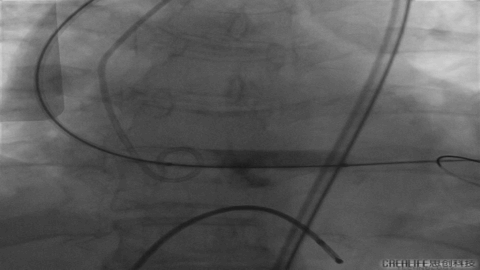

Nmued20预扩1

Nmued20预扩2